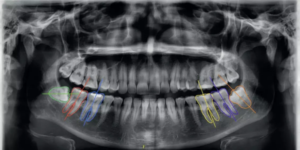

AI system improves accuracy of CBCT images for implant placement, third molar extraction and orthognathic surgery: Study

AI system improves accuracy of CBCT images for implant placement,…